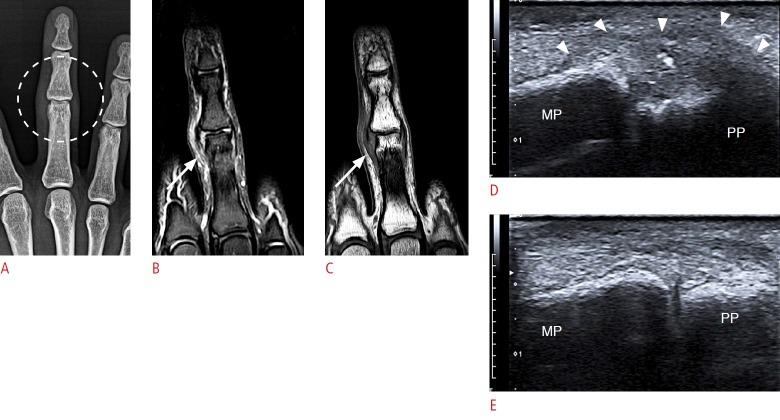

The recent development of advanced high-resolution transducers has enabled the fast, easy, and dynamic ultrasonographic evaluation of small, superficial structures such as the finger. In order to best exploit these advances, it is important to understand the normal anatomy and the basic pathologies of the finger, as exemplified by the following conditions involving the dorsal, volar, and lateral sections of the finger: sagittal band injuries, mallet finger, and Boutonnière deformity (dorsal aspect); flexor tendon tears, trigger finger, and volar plate injuries (volar aspect); gamekeeper's thumb (Stener lesions) and other collateral ligament tears (lateral aspect); and other lesions. This review provides a basis for understanding the ultrasonography of the finger and will therefore be useful for radiologists.

先进的高分辨率换能器的最新发展使得对手指等小而浅表结构进行快速、简便和动态的超声评估成为可能。为了充分利用这些进展,了解手指的正常解剖结构和基本病变非常重要,以下列举了累及手指背侧、掌侧和侧方的一些情况,包括:矢状带损伤、锤状指和纽扣畸形(背侧);屈肌腱撕裂、扳机指和掌板损伤(掌侧);守猎者拇指(斯滕纳损伤)和其他侧副韧带撕裂(外侧);以及其他病变。这篇综述为理解手指的超声检查提供了基础,因此对放射科医生非常有用。